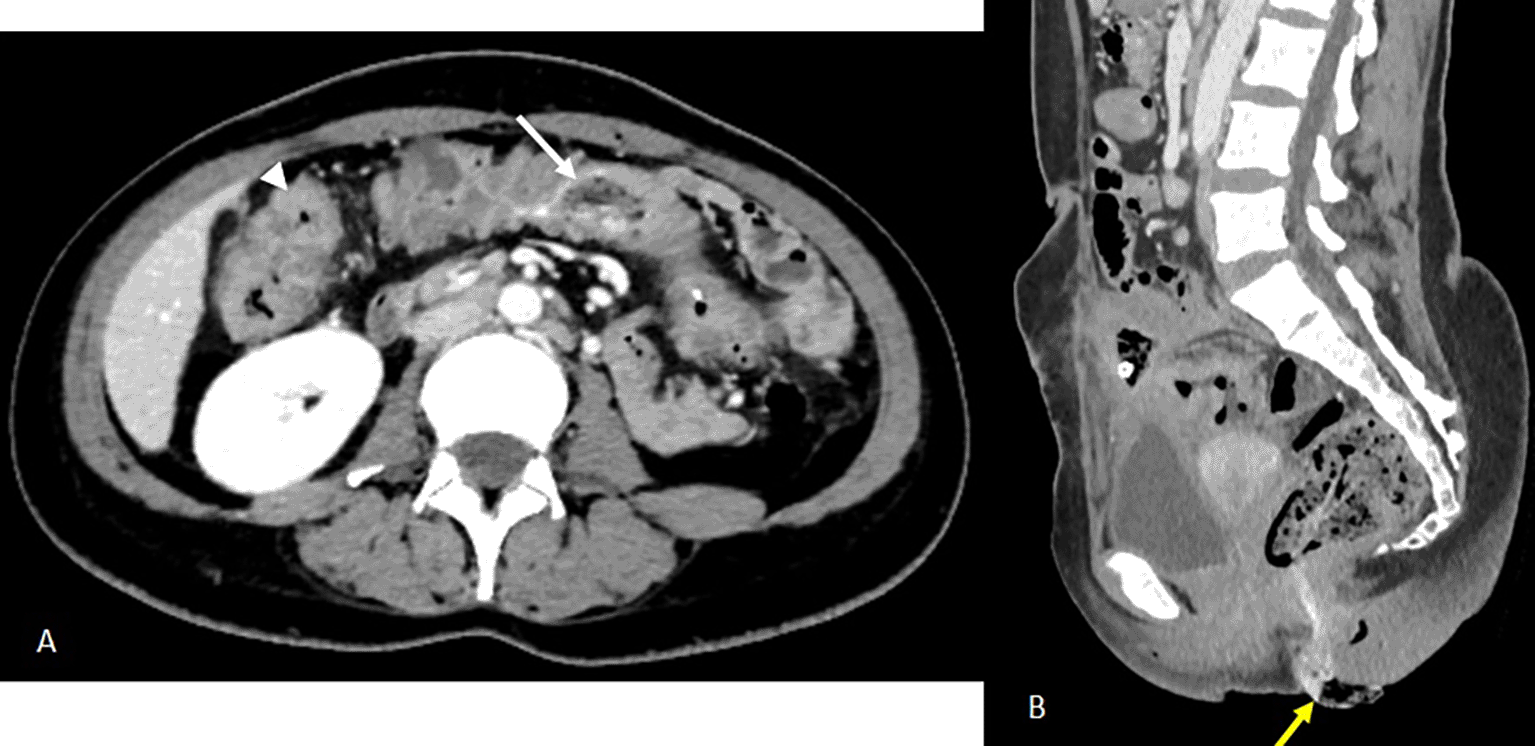

On day 13 of continuing intravenous antibiotics, the patient reported a sensation of rectal fullness. Rectal exam revealed a textile foreign body soiled with feces. An abdominal CT scan was ordered. It confirmed the progressive migration of both foreign bodies, described in a heterogeneous mass containing gas bubbles and air-filled linear or wavy radiodensities, along the colon, one reaching the transverse colon and the other component extended toward the rectosigmoid and externally protruded distally through the anal margin (Figure 3). Rigid rectoscopy on day 18 confirmed retained gauze embedded in the rectal mucosa approximately 20 cm from the anal verge (Figure 4), which was extracted under visual guidance (Figure 5). Following extraction, the patient developed acute diffuse abdominal pain and guarding.

There is also evidence of regular pancolic wall thickening (white arrowhead) and a stable inflammatory complex in the small bowel loops and surrounding fat.

B- Sagittal reconstruction in the portal phase partially illustrating the second foreign body, which has continued to migrate to the rectosigmoid colon (previously in the left colon), the distal end of which is externalised through the anal margin (yellow arrow).